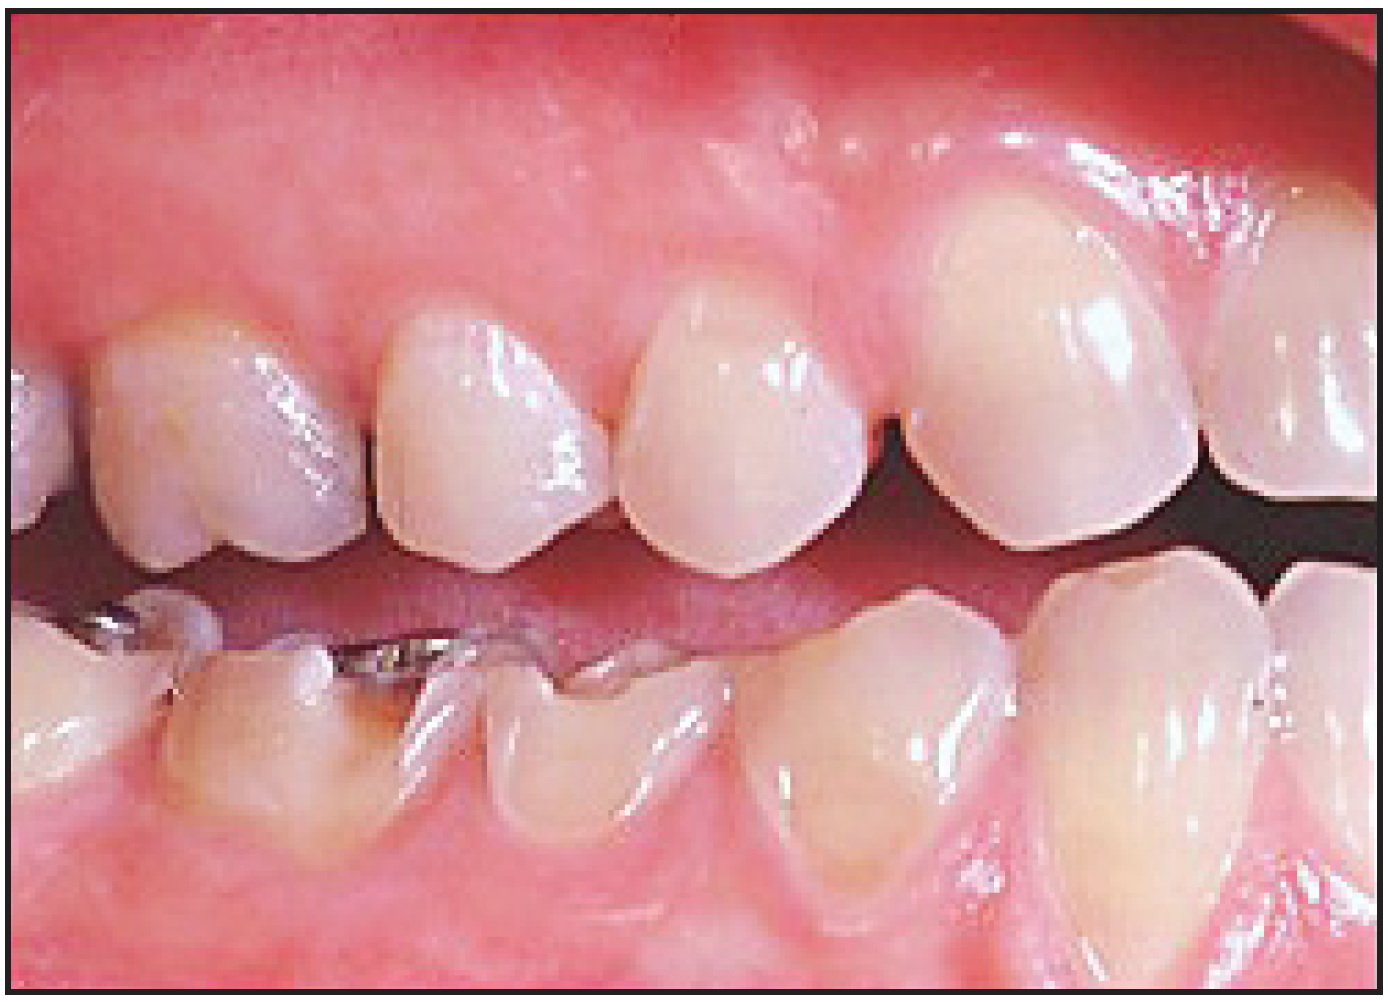

The potential ravages of soda pop caries in teenagers should not be underestimated. Some teenagers drink as many as 12 cans of soda pop a day. In one well-documented case, a teenager who grew up drinking fluoridated water and brushing twice daily with a fluoride-containing toothpaste developed caries in every one of his erupted teeth, necessitating two extractions and many restorations. Diet analysis revealed that he consumed 6-12 cans of soda pop daily.4 Some of the ravages of this condition are visible in Figure 2 and Figure 3. Other case reports have demonstrated similar findings among other adolescents in whom chronic, high soda pop consumption was linked with widespread demineralization of enamel and extensive caries in pits and fissures and in the interproximal areas.5

Figure 2 – Erosion Due to Soda Pop Consumption.<sup>25</sup>

Figure 2